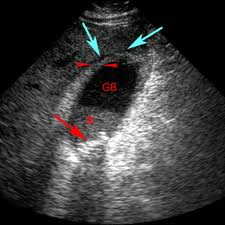

Soi cổ tử cung là thủ thuật dùng một camera đặc biệt để khảo sát bất thường của âm đạo và phần ngoài của cổ tử cung.

- Bác sĩ dùng mỏ vịt để bộc lộ âm đạo và cổ tử cung, sau đó sẽ hướng máy soi vào và quan sát từ âm hộ, âm đạo, cổ tử cung.

- Khi soi, bác sĩ có dùng một số hóa chất như Acid Acetic và Lugol để bôi lên vùng ngoài cổ tử cung. Những hóa chất này giúp cho những biểu hiện bất thường của cổ tử cung thể hiện rõ hơn.